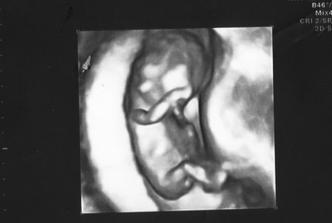

Priletí k nám bocian